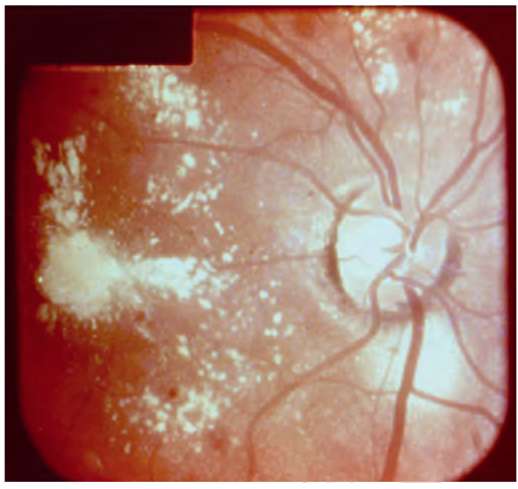

Рис. 26.1. Центральный токсоплазмозный хориоретинит

Рис. 26.2. Гранулематозный токсоплазмозный хориоретинит